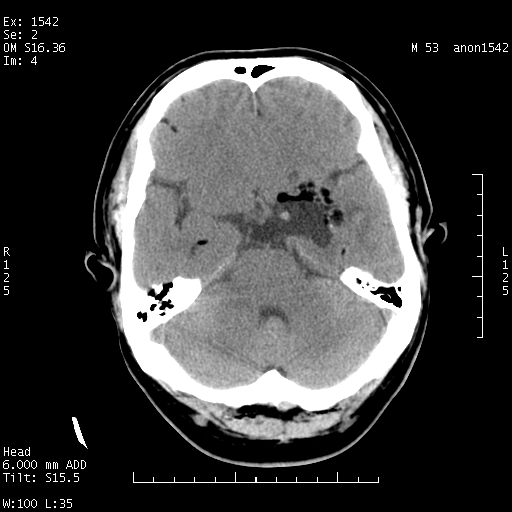

标题: CT10811:M53Y,头痛一月.其它没有什么 [打印本页]

左侧鞍旁不规则低密度,此区域和侧脑室有液平。若无外伤史。考虑左侧鞍旁表皮样囊肿自发破溃。

鞍旁颞叶低密度灶.其中散在空气影.还有侧脑室.是否考虑脑脓肿(请提供病史情况)

1.支持考虑左侧鞍旁表皮样囊肿自发破可能;

有肿瘤样病变破溃,沿外侧裂生长,为什么不考虑胆脂瘤?

1 囊性肿物. 2 请楼主上传介少病人资料. 3 表皮样囊肿或胆脂瘤都在考虑范围内,确切的不知ct值是多少.4了解病史后在缺定.

考虑:左侧鞍旁表皮样囊肿自发破溃,是否合并感染?